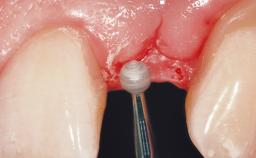

A 30-year-old female patient had lost tooth 21 and was referred to our clinic for consultation and treatment. Due to advanced apical infection, tooth 21 had been extracted two months earlier at another clinic and an acrylic-resin tooth had been bonded to the adjacent teeth. The patient desired implant treatment to avoid any damage to the adjacent natural teeth. While the patient had no history of any systemic disorder, she was a heavy smoker and exhibited medium to advanced periodontitis in the entire jaw. After the initial treatment to achieve a pocket probing depth of less than 4 mm and no bleeding on probing, a decrease in the height of the papillae mesial and distal to the extraction site and overall gingival recession were observed.

Soft Tissue Grafting Simultaneous

Abutment Type CAD/CAM

Prosthesis Type FDP